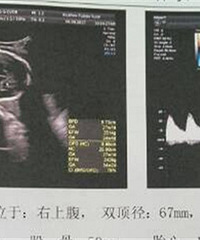

现在已经孕24周+了,本来只是说试一次,看能不能中,平时月经还是蛮准的,然后当月月经推迟了2天,买了试纸,两条杠杠,超级明显,去医院验了HCG3万多